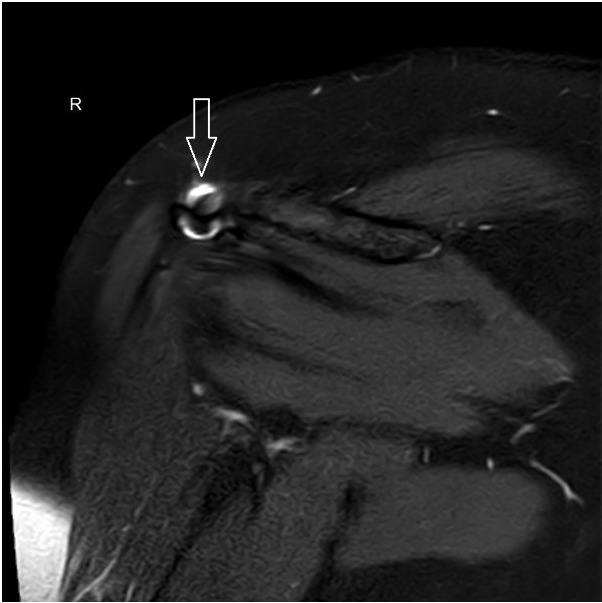

Hier geht's zum Quizfall: http://docc.hk/schulter